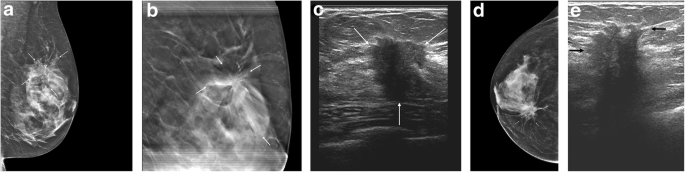

50.6% of patients completed their assessment on the initial visit (as exemplified in Fig. 1), 39.0% on the second visit, 9.1% on the third visit and 1.3% on the fourth visit (Table 3). A total of 34 patients underwent image-guided biopsies, 16 (47.1%) of which yielded malignant results (Table 4).

Fig. 1

figure 1

Fifty-four-year-old woman presented with palpable regions in both breasts. All imaging tests and biopsies were completed on a single visit. Left breast: a left breast mediolateral oblique projection from the initial mammogram shows architectural distortion in the upper aspect of that breast (arrows). b Spot tomosynthesis view of the upper-left breast shows persistence of the architectural distortion (arrows). c On left breast ultrasound, the architectural distortion corresponds to a 1.9-cm solid mass (arrows). Right breast: d right breast craniocaudal projection from the initial mammogram shows a spiculated mass (arrows) associated with pleomorphic calcifications (arrowheads) in the medial right breast. e On right breast ultrasound, this corresponds to a 2.9-cm solid mass (arrows). Bilateral ultrasound core biopsies showed bilateral invasive ductal carcinomas. The pathology report was available 4 days later at which time the patient was contacted by a breast surgeon to discuss a treatment plan. The surgery was performed 10 days after the pathology results were available